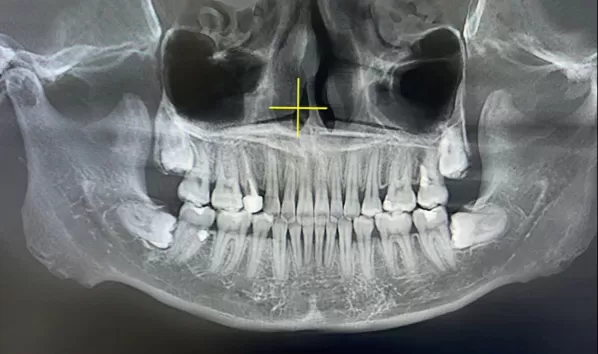

Rayons X avant le traitement

[Radiographie panoramique/Céphalogramme latéral]